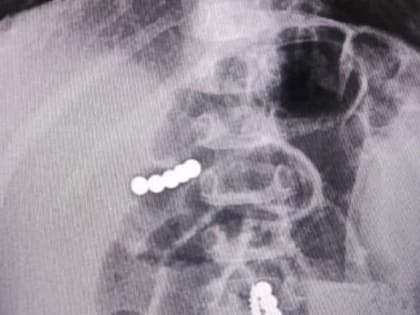

Инновационную методику лечения запатентовали нейрохирурги Ставрополя

Специалисты клинической больницы скорой медпомощи Ставрополя получили патент на прорывное изобретение в области лечения травм спинного мозга.